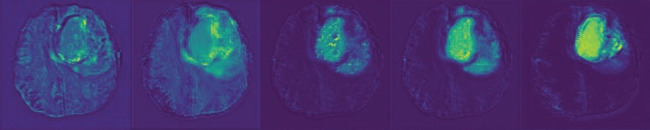

Accurate brain tumor segmentation is essential for clinical decision-making, yet remains difficult to automate. Key obstacles include the small volume of lesions, their morphological diversity, poorly defined MRI boundaries, and nonuniform intensity profiles. Furthermore, while traditional segmentation approaches often focus on intralayer relevance, they frequently underutilize the rich semantic correlations between features extracted from adjacent network layers. Concurrently, classical attention mechanisms, while effective for highlighting salient regions, often lack explicit mechanisms for directing feature refinement along specific dimensions. To solve these problems, this paper presents CAGs-Net, a novel network that progressively constructs semantic dependencies between neighboring layers in the UNet hierarchy, enabling effective integration of local and global contextual information. Meanwhile, the channel attention gate was embedded within this adjacent-context network. These gates strategically fuse shallow appearance features and deep semantic information, leveraging channel-wise relationships to refine features by recalibrating voxel spatial responses. In addition, the hybrid loss combining generalized dice loss and binary cross-entropy loss was employed to avoid severe class imbalance inherent in lesion segmentation. Therefore, CAGs-Net uniquely combines adjacent-context modeling with channel attention gates to enhance feature refinement, outperforming traditional UNet-based methods, and the experimental results demonstrated that CAGs-Net shows better segmentation performance in comparison with some state-of-the-art methods for brain tumor image segmentation.